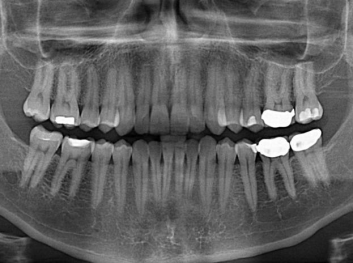

損壞的牙齒如何自我修復(fù)?近日,來(lái)自哈佛大學(xué)和諾丁漢大學(xué)的研究人員研發(fā)了能夠刺激牙齒干細(xì)胞再生的新型生物材料,而這種新材料研發(fā)成功的背后,正源于他們對(duì)牙齒如何實(shí)現(xiàn)自我修復(fù)這個(gè)課題的不斷探索。

據(jù)美國(guó)期刊《大眾科學(xué)(Popular Science)》報(bào)道,此種新型生物材料,不僅可以有效地取代傳統(tǒng)補(bǔ)牙填充物,刺激牙齒干細(xì)胞再生,患者也有望無(wú)需再接受根管治療,使蛀牙患者免除牙根感染或牙髓壞死的苦惱,一個(gè)全新的牙齒治療時(shí)代即將來(lái)臨。

Adam Celiz,是來(lái)自諾丁漢大學(xué)的研究人員,他和同事開(kāi)發(fā)的這種新型合成生物材料,能刺激干細(xì)胞在牙髓部的生長(zhǎng)。與普通材料一樣,這種合成材料被填充到牙齒并用UV光硬化。

在體外測(cè)試中,材料刺激干細(xì)胞進(jìn)入牙本質(zhì)的增殖和分化速度,促進(jìn)形成牙齒骨組織。研究人員認(rèn)為,一旦材料在受損牙齒中應(yīng)用,這些干細(xì)胞可以自動(dòng)修復(fù)來(lái)自填充物上的損壞。在本質(zhì)上,該生物材料將使牙齒自愈。

在未來(lái),Adam Celiz說(shuō),可再生材料能制成各種填充物以便受損牙齒的自身治愈,降低補(bǔ)牙失敗率,甚至?xí)蟛糠秩藢?duì)根管治療的需要。